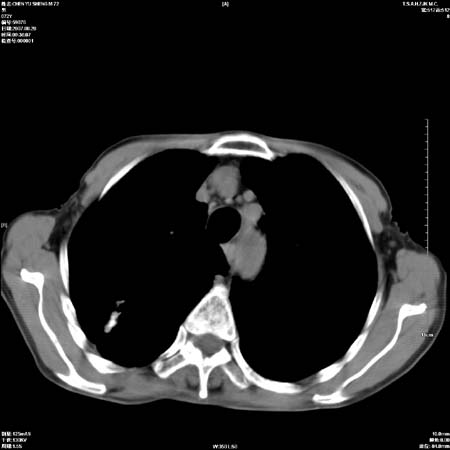

男性,72岁,既往肺结核,今复查。无前片对比。

纵隔窗

右侧中央型肺癌伴中叶不张可能性大,建议增强扫描.右上肺陈旧性肺结核.慢性支气管炎伴肺气肿.右侧少量胸腔积液.

右侧中央型肺癌伴中叶不张可能性大,建议纤支镜检查.右上肺陈旧性肺结核.肺气肿。

典型右肺中心型肺癌

右侧中央型肺癌伴肺不张可能性大,建议增强扫描.右上肺陈旧性肺结核.慢性支气管炎伴肺气肿.右侧少量胸腔积液.

右肺中心型肺癌

右侧中央型肺癌.上肺陈旧性肺结核.

1右侧中央型肺癌伴中叶不张2右侧少量胸腔积液3右上肺陈旧性肺结核

1.右肺中心性肺癌并右肺中叶综合征2。右侧胸腔少量积液3。右肺上叶结核球已钙化,4。慢支伴肺气肿

右侧中央型肺癌伴中叶不张可能性大,建议纤支镜检查.右上肺陈旧性肺结核.肺气肿。

右侧中央型肺癌伴中叶不张可能性大,建议增强扫描.右上肺陈旧性肺结核.慢性支气管炎伴肺气肿.右侧少量胸腔积液.

右侧中央型肺癌伴中叶不张

右肺中央型肺癌伴右肺中叶不张。

右上肺陈旧性肺结核。

支持右肺中心型肺癌并中叶不张,右上肺陈旧性肺结核钙化,右侧少量胸腔积液。

支持右侧中央型肺癌伴中叶不张可能性大,建议增强扫描.右上肺陈旧性肺结核.慢性支气管炎伴肺气肿.右侧少量胸腔积液.

支持 1右侧中心型肺癌伴中叶不张2右侧少量胸腔积液3右上肺陈旧性肺结核4双肺局限性肺气肿

1,右侧中央型肺癌.

2,右上肺陈旧性肺结核.

1.右侧中央型肺癌伴中叶不张,建议纤支镜检查.

2.右上肺陈旧性肺结核.

3.肺气肿。

4.右侧少量胸腔积液.

右侧中央型肺癌伴中叶不张并纵隔淋巴结增大,建议增强扫描.右上肺陈旧性肺结核.慢性支气管炎伴肺气肿.右侧少量胸腔积液。

右肺中心型肺癌并肺不张,陈旧性肺tb.慢支,肺气肿.

陈旧性肺结核.慢性支气管炎伴肺气肿,中央型肺癌伴中叶不张。

右侧中央型肺癌伴中叶不张可能性大;右上肺陈旧性肺结核.慢性支气管炎伴肺气肿

陈旧性结核是存在,但真正致命的却是右侧中心型肺癌。